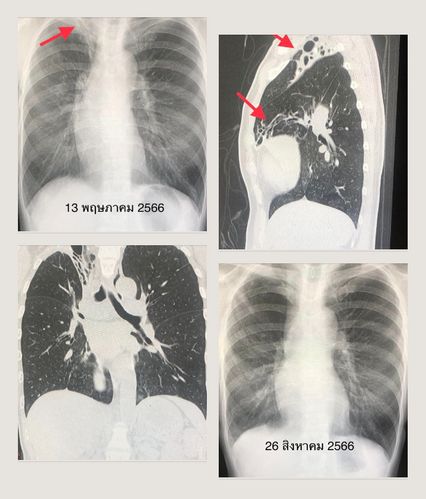

วัณโรคเทียม วันนี้ (26 ก.ย.66) นพ.มนูญ ลีเชวงวงศ์ แพทย์เฉพาะทางด้านโรคระบบทางเดินหายใจ-ผู้ป่วยอาการหนัก เปิดเผยผ่านเฟซบุ๊กส่วนตัวถึงการติดเชื้อวัณโรคเทียม โดยยกเคสผู้ป่วย เพศหญิงอายุ 48 ปี เคยมีประวัติป่วยเป็นวัณโรคปอด เมื่อ 14 ปีที่แล้ว รักษานาน 9 เดือน ผู้ป่วยไอเป็นเลือดครั้งแรกเมื่อ 4 ปีก่อน และปีที่แล้ว ก็ไอเป็นเลือด เดือน เม.ย.66  ผู้ป่วยก็ไอเป็นเลือด ที่โรงพยาบาลอื่นตรวจเสมหะเพาะเชื้อวัณโรค พบเชื้อวัณโรคเทียม Mycobacterium abscessus แต่ไม่ได้ตรวจหาความไวต่อยา ผู้ป่วยมา รพ.วิชัยยุทธ ในเดือน พ.ค.66 ด้วยอาการไอเป็นเลือดสด ไม่เหนื่อย น้ำหนักไม่ลด ไม่มีไข้ พร้อมให้ประวัติไม่เคยสูบบุหรี่

ผลตรวจร่างกายปกติ เอกซเรย์ปอดด้านบนขวาผิดปกติ เอกซเรย์คอมพิวเตอร์ปอดพบหลอดลมโป่งพองที่ปอดขวากลีบบนและกลีบกลาง ตรวจสมรรถภาพปอด ผลปกติ  ส่งเสมหะเพาะเชื้อวัณโรค ขึ้นเชื้อวัณโรคเทียม เนื่องจากปริมาณน้อยไม่สามารถบอกได้ว่าเป็นเชื้ออะไร และไม่สามารถตรวจหาความไวต่อยา

แพทย์วินิจฉัย ว่าการไอเป็นเลือดมาจากโรคหลอดลมโป่งพอง ซึ่งเป็นผลข้างเคียงจากการป่วยเป็นวัณโรคเมื่อ 14 ปีก่อน ต่อมาติดเชื้อวัณโรคเทียมจากสิ่งแวดล้อม เนื่องจากผู้ป่วยไอเป็นเลือดหลายครั้ง บางครั้งก็มีเลือดออกปริมาณมาก และพยาธิสภาพของโรคนี้จำกัดอยู่ในปอดขวากลีบบนและกลีบกลาง การผ่าตัดเอาปอดขวากลีบบนและกลีบกลางออก จะช่วยป้องกันการไอเป็นเลือดซ้ำแล้วซ้ำอีก และช่วยป้องกันไม่ให้เชื้อวัณโรคเทียมกระจายไปส่วนอื่นๆของปอด

หมอมนูญ เผยว่าแพทย์ได้ทำการผ่าตัดเอาปอดขวากลีบบนและกลีบกลางออกด้วยการส่องกล้อง เมื่อวันที่ 5 ส.ค.66 ได้ให้ยารักษาวัณโรคเทียม Mycobacterium abscessus ด้วยยากิน clarithromycin และยาฉีด amikacin, tigecycline ก่อนและหลังผ่าตัดระหว่างอยู่ในโรงพยาบาล ระหว่างวันที่ 4-9 ส.ค.66 เพื่อป้องกันวัณโรคเทียมแพร่กระจายไปส่วนอื่นในปอดระหว่างผ่าตัด

วันที่ 26 สิงหาคม ผู้ป่วยสบายดี ไม่มีไข้ ไม่ไอ ไม่เหนื่อย แผลผ่าตัดแห้งดี เอกซเรย์ปอดดีขึ้นมาก (ดูรูป) ผลเพาะเชื้อวัณโรคจากเนื้อปอด ขึ้นเชื้อวัณโรคเทียม Mycobacterium abscessus ไวต่อยา amikacin และ clarithromycin เนื่องจากได้ตัดปอดส่วนที่ติดเชื้อไปแล้ว จึงยังไม่ให้ยารักษาวัณโรคเทียมขณะนี้ ติดตามใกล้ชิดต่อไป อาจต้องให้ยาในภายหลัง